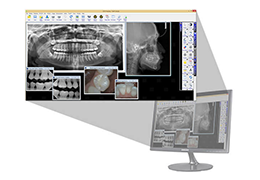

View X-Ray CT & MRI Scans Fast and Easily

Designed for surgeons, Pro Surgical 3D makes it easy to view patient scans quickly. Pro Surgical 3D facilitates the optimal 3D treatment and assessment workflows based on X-ray CT and MRI scans – and best of all, it’s FREE!

Everyone – including surgeons, patients and their loved ones – benefits from being better informed by the wealth of information buried within CT and MRI scans. Pro Surgical 3D gives surgeons more information to develop optimal treatment plans for patients. It also helps patients and their support group better understand their medical condition and proposed treatment options.

Better understanding of a condition, disease or diagnosis

Ability to clearly see the condition or disease

Better understanding of treatment options

Better grasp of treatment progress by comparing scans over time

Very fast and easy to use

Load DICOM data directly from PACS, CD/DVD, USB, and local computer.

Easy to use patient search to locate patient data on your PACS.